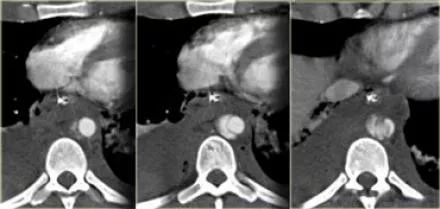

CT增强扫描,提高病灶检出率

CT增强扫描是一种在CT检查过程中注入对比剂,以增强病灶与周围组织对比度的检查方法。其优势如下:

提高病灶检出率:CT增强扫描可以清晰显示等密度病灶和小病灶,提高诊断准确性。

提高定性诊断能力:CT增强扫描有助于判断病灶的良恶性,为医生制定治疗方案提供依据。

提高肿瘤分期准确性:CT增强扫描有助于判断恶性肿瘤的分期,为手术切除和治疗后疗效评价提供参考。

鉴别血管源性病变:CT增强扫描有助于鉴别血管源性病变,如肺门、颈部、盆腔等部位的血管与淋巴结。